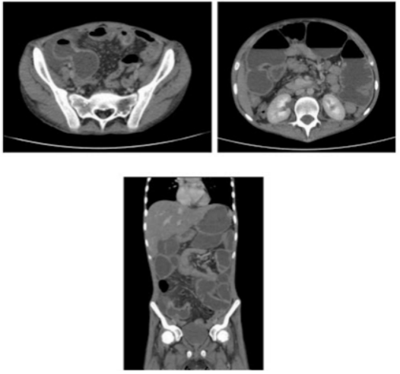

Paciente de 17 anos, IMC: 20 kg/m², vai ao pronto-socorro com dor abdominal difusa há 6 meses, contínua, de leve a moderada intensidade, associada a diarreia intermitente, náuseas e vômitos, inapetência, perda ponderal importante e edema de membros inferiores até raiz de coxa. Piora súbita da dor abdominal há 1 dia, localizada em epigástrio e mesogástrio, em cólica. Nega febre, nega demais queixas. Sem morbidades, internações ou cirurgias prévias. Ao exame físico: Regular estado geral, descorado, desidratado, afebril, anictérico, acianótico, eupneico, taquicardíaco e caquético. Abdome plano, tenso (em tábua), descompressão brusca positiva. Os membros mostram edema simétrico até joelho 2+/4+, compressível. Exames laboratoriais: Hemoglobina: 9,1 g/dL, Leucócitos: 21.650/mm³ (Neutrófilos: 94%, bastonetes: 10%; 84% segmentado), albumina: 3,9 g/dL. Foi submetido a tomografia, conforme imagem. Submetido a laparotomia mediana não houve instabilidade hemodinâmica durante a operação. Os achados foram os seguintes: moderada quantidade de líquido purulento em goteira parietocólica direita e pelve. Grande dilatação de alças jejunais a 1,80 m do ângulo de Treitz, evidenciado segmento de 60 cm de jejuno contendo sete áreas estenóticas, sendo a mais proximal perfurada e bloqueada na sua borda contra mesentérica, recoberta por fibrina. Cólon hipoplásico em toda sua extensão (desuso). Restante dos órgãos e estruturas de aspecto macroscópico normal. Melhor conduta, dentre as abaixo: